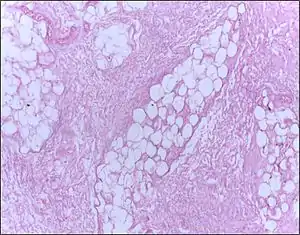

| Micrograph of breast tissue showing fat necrosis. H&E stain | |